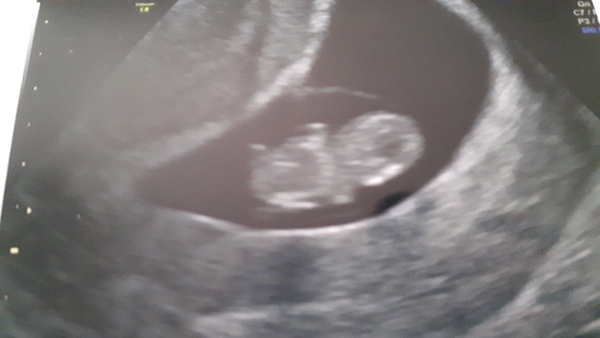

Saw little blob this morning! Strong heartbeat, you could see it fluttering away, and it's exactly the size it should be for 8 weeks 6 days (a whole 2mm!), so very reassured and excited. :) Even stoic as all DH cracked a smile. Eeeeeeh!

@wordsmithereens cutie!! Looks fantastic. And don't do yourself down - it's 2cm! Blows my mind that a month ago they were just the size of a poppyseed and now they are practically baby-shaped.

What a lovely scan picture @wordsmithereens

Beautiful scan @wordsmithereens how lovely 😊

Thanks guys! :) @ladycarlotta, definitely not doing myself down, I'm mostly seriously impressed how something so small has so much power to make you feel so crap. Grin And you're right, when you think about it it's amazing how rapidly they grow in the first few months. You could even see the hands!

@wordsmithereens such a lovely picture!

Fantastic scan @wordsmithereens congratulations!